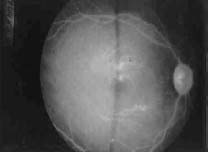

El diagnóstico de sospecha de la enfermedad es clínico, siendo obligado examinar el fondo de ojo, donde aparece una imagen típica, la lipemia retinalis (Figura 2), caracterizada por vasos de coloración rosa pálido debido al aumento de los quilomicrones.1,3,7 La ateroesclerosis precoz no es un hallazgo frecuente.

Figura 2. Lipemia Retinalis7